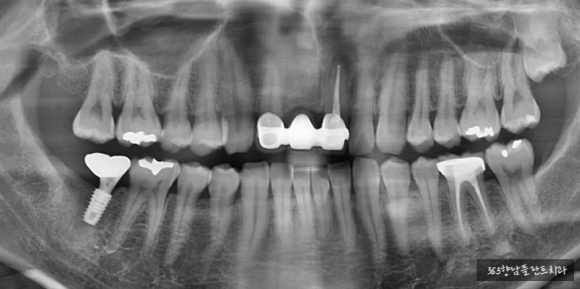

24.06.21 잇몸뼈 회복으로 신경관 상방 치조골 6.2mm 확보

약 3개월 정도 기다리는 동안 신경 위로 약 6.2mm의 잇몸뼈가 확보된 것을 확인하고 신경관 임플란트 식립을 진행하였는데요.

저희 의료진과 정기적으로 소통하시며 잘 협조해 주신 환자분 덕분에 13.5mm의 초기 고정력을 얻기 충분한 길이의 임플.란트를 심을 수 있었습니다.

24.06.21 임플란트 식립

24.03.02 치료 전

24.06.21 식립 후

24.10.18 치료 완료

인공치아 뿌리 식립 후 잇몸뼈와 충분히 고정되는 것을 기다린 후 기둥을 세우고 신경관 임플란트 치료를 완료하였습니다.